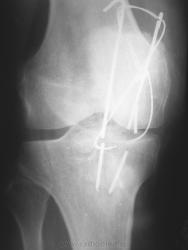

Пол пациента: Мужской пол Тип патологии: Травма Область исследования: Скелетно-мышечная система Методы исследования: Rg После операции. И так бывает, пациент жалоб не предъявляет https://radiomed.ru/sites/default/files/styles/case_slider_image/public/user/6152/2000.jpg?itok=kpUbJZyq https://radiomed.ru/sites/default/files/styles/case_slider_image/public/user/6152/2002.jpg?itok=ekIs4rwy https://radiomed.ru/sites/default/files/styles/case_slider_image/public/user/6152/2003.jpg?itok=G7ZQHQ9V ID:7928 Втр, 12/10/2010 - 14:10 #1 Александр Викторович Не на сайте Был на сайте: 8 лет 2 дня назад Зарегистрирован: 31.07.2010 - 13:05 Публикации: 639 летать будет проблематично, в смысле авиаперелетов... Втр, 12/10/2010 - 20:53 #2 stovbav Не на сайте Был на сайте: 2 года 2 месяцев назад Зарегистрирован: 20.12.2009 - 17:28 Публикации: 7066 Раз жизнь "обломала" то и травматологи не стали ей перечить, пошли тем же путем, да, очевидно, и правильно сделали. Болезни ног: виды, симптомы, причины, профилактика и лечение